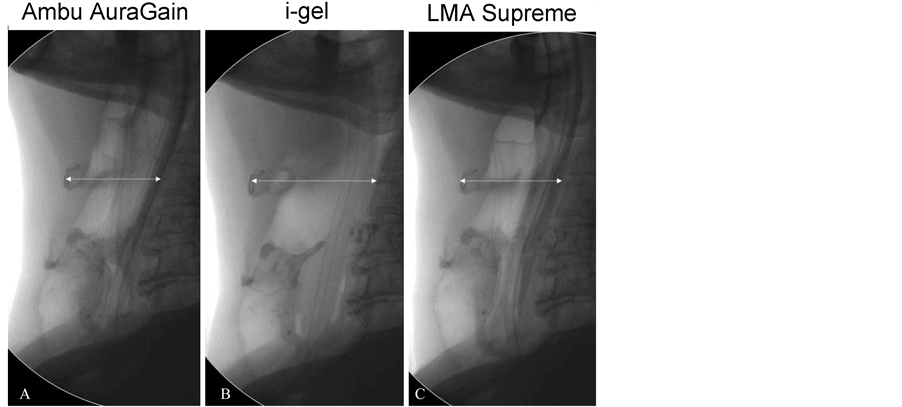

Lateral X-ray of neck confirmed the correct final position of the three devices in relation to the airway and the placement gastric tube into the esophagus (Figure 3).

The anterior displacement of the hyoid bone and laryngeal structures was more evident with the i-gel when the volume needed to achieve an intracuff pressure of 60 cm H2O was low with the AuraGain and LMA Supreme (Figure 3). Interestingly, the proximal edge of the cuff of the size 5 AuraGain appeared slightly wrinkled in two cadavers in comparison to the cuff of size 5 LMA Supreme (Figure 4).

Figure 3. Lateral X-Ray images of the three devices (size 4) in the same cadaver. (A) AmbuAuraGain; (B) Intersurgical i-gel; (C) LMA Supreme. The arrows show the distance from the spine to the hyoid bone. The cuffs of the AuraGain and the LMA Supreme were both inflated to 60 cm H2O causing less anterior displacement of the perilaryngeal structures.